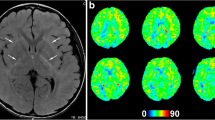

Clinical outcome at the end of the first month

Negative significant correlation was found between imaging score and GOS (R = −0.67, P < 0.001) in the LRD (+) group (Fig. 4a). No significant correlation was found between imaging score and GOS in the LRD (−) group.

Clinical outcome at the end of the 12th month

Negative significant correlation was found between imaging score and GOS (R = −0.56, P = 0.001) in the LRD (+) group (Fig. 4b). No significant correlation was found between imaging score and GOS in the LRD (−) group.

Concerning imaging score, multivariate logistic regression analysis showed imaging score to be a significant risk factor for unfavorable outcome only at 12th month follow-up (P < 0.043), in which subgroup III had a higher risk for unfavorable outcome (OR, 4.70; P = 0.20) when compared with subgroup I (Table 2). In the LRD (+) group, significant negative correlation was found between imaging score and GOS at both 1st month and 12th month follow-up (Fig. 4). On the other hand, in the LRD (−) group, no significant correlation was found between imaging score and GOS. Thus, our results suggest that the extent of abnormality, represented by imaging score, has greater clinical significance in the LRD (+) group than that in the LRD (−) group and also greater significance at long-term follow-up.